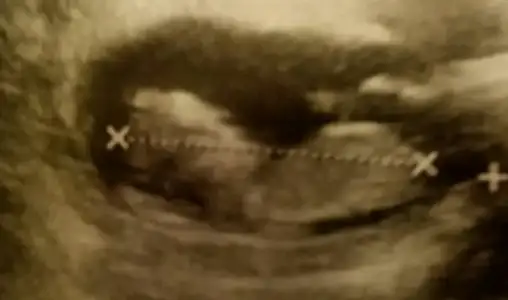

Kızlar buda benim ponçiğim bi türlü resmini koyamamıştım ama sonunda başardım. Ikili tests gunu cekilmis fotolari 11+6 idi o gun ama ultrasonda 12+3 çıķmıştı. Doktor erkege benzio demisti dikkat ettimde resimde bülüşünü gördüm ben sağ üstteki resmde